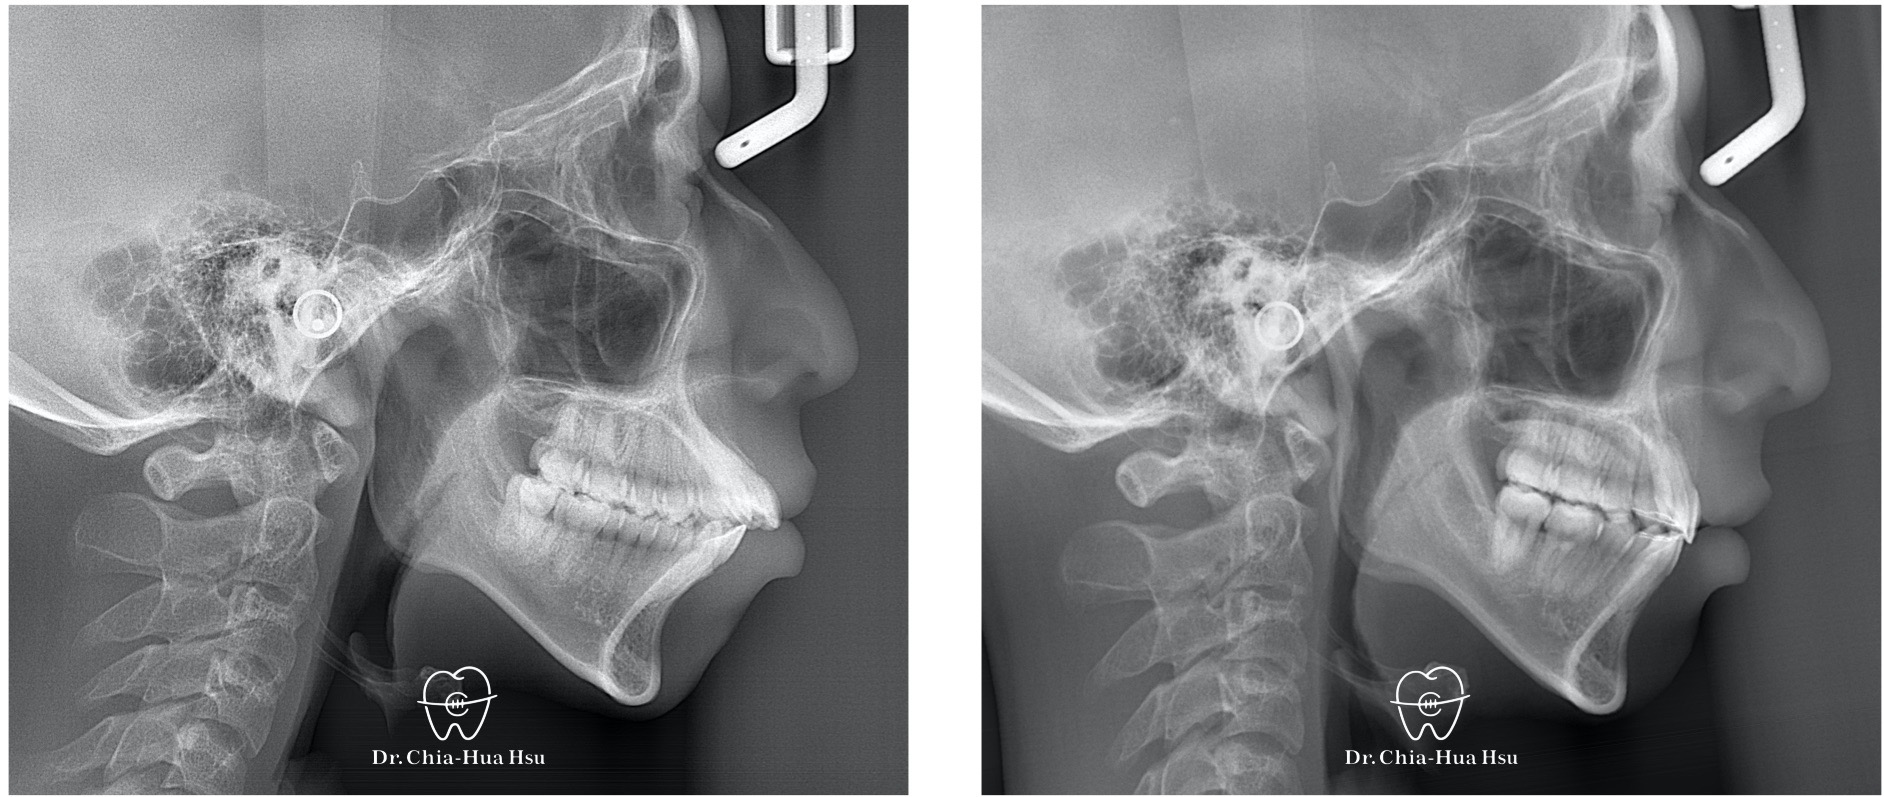

治療前

治療後

- 問題分析:患者是嚴重的骨骼二類咬合(Skeletal Class II)、下巴後縮、暴牙以及齒列不整齊。

- 治療方式:使用傳統金屬矯正器,並拔除四顆小臼齒,配合多支暫時性迷你骨釘來完成治療。